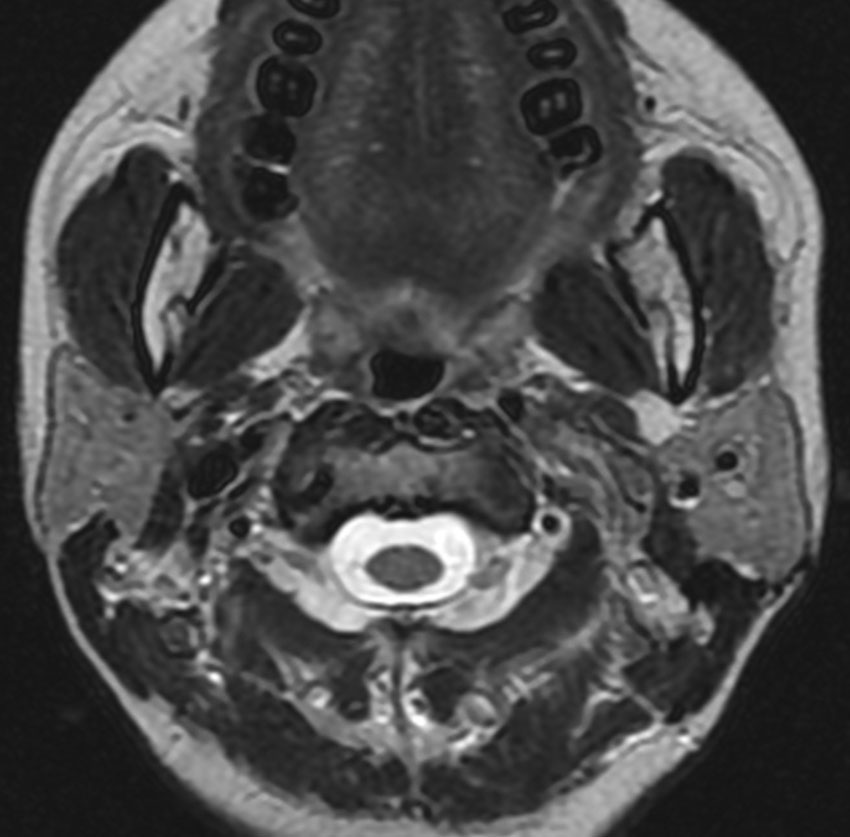

症例:頸静脈孔より下の深頸部のもの:副咽頭間隙腫瘍

左頸静脈孔の下の迷走神経節から発生したものです。ごく軽い飲み込み辛さだけが症状でした。

内頚動脈を強く圧排して,外形動脈からはかなり豊富な血流が流入しています。頭頸部外科で顎骨を割るような手術を計画されていました。

でも,右側の画像で見るような角度から,小さな頸部の皮膚切開だけで,胸鎖乳突筋だけを乳様突起から外して翻展して摘出できました。内部からほじくるように摘出すれば症状悪化はないのですが,周囲軟部組織から切断して剥離しようとすると厳しい嚥下障害と嗄声になります。

手術で全摘出しましたが嚥下障害などはでませんでした。普通のおとなしい神経鞘腫ですから再発はありません。